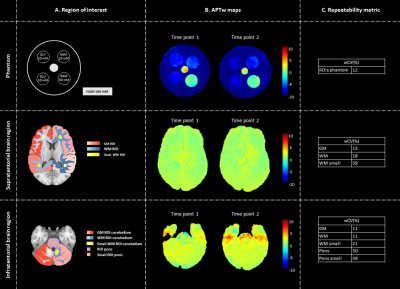

To assess the repeatability, APTw imaging is performed twice with an interval of one week. APTw maps were acquired for a cylindrical phantom (filled with 0.9% saline solution and five submerged falcon tubes at pH ~7.0) and in five healthy volunteers (2m/3f; age:25.8±1.7 years) in supratentorial and infratentorial brain region (Fig.1A).

The repeatability was quantified by calculating the within-coefficient-of-variation (wCV). Regions of interest (ROIs) were defined by manual delineation (phantom) and by applying atlas-based segmentation using the MNI-152 atlas11,12 and Elastix13(healthy volunteers)(Fig.1A).

Similar APTw levels were acquired for both time points for all ROIs of the phantom and supratentorial and infratentorial brain region, supported by the wCV (Fig.1). In small WM ROIs the wCV increased by 50% with respect to WM ROIs. In addition, B0-inhomogeneities affect the repeatability, resulting in high wCV, i.e. worse repeatability, in the pontine region. Phantom data indicated that APTw maps are specific for amides.

Figure 1: Repeatability of APTw imaging of the phantom (top), supratentorial brain region (middle) and infratentorial brain region (bottom). For the phantom, supratentorial brain region and infratentorial brain region an overview of ROIs (A), APTw maps for two time points (B) and repeatability metric (wCV)(C) are illustrated.